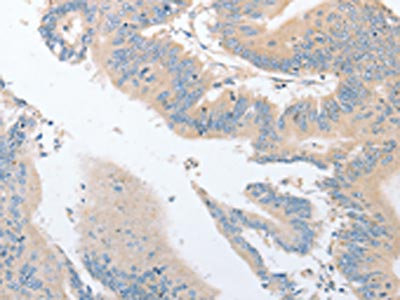

The image on the left is immunohistochemistry of paraffin-embedded Human thyroid cancer tissue using CSB-PA524180(EPS15L1 Antibody) at dilution 1/30, on the right is treated with fusion protein. (Original magnification: ×200)

The image on the left is immunohistochemistry of paraffin-embedded Human colon cancer tissue using CSB-PA524180(EPS15L1 Antibody) at dilution 1/30, on the right is treated with fusion protein. (Original magnification: ×200)